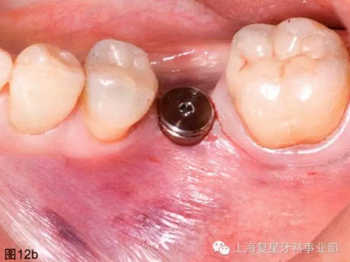

通過(guò)導(dǎo)板的引導(dǎo),以15prm,50Ncm旋入種植體。一旦種植體到達(dá)最后的深度(圖12a),去除種植手機(jī)和攜帶器,然后將一個(gè)愈合基臺(tái)(BioHorizons,直徑4.5毫米×長(zhǎng)3毫米)擰在種植體上(圖12b)。軟組織打孔器取出的軟組織進(jìn)行結(jié)締組織移植,然后放置在一個(gè)頰楔上獲得一定體積和厚度的角質(zhì)化軟組織(圖12c)。無(wú)需縫合。術(shù)后拍攝X片,對(duì)種植體的最終位置進(jìn)行評(píng)估。

圖12b:已放入愈合基臺(tái)